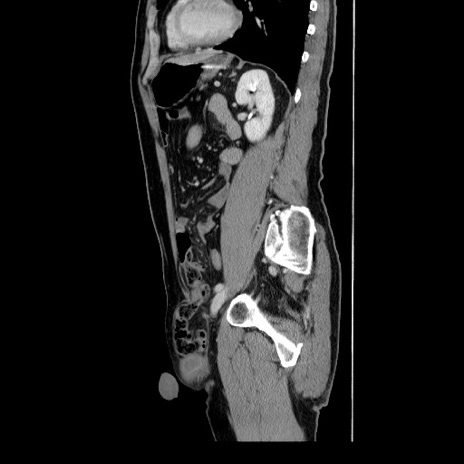

症例34(矢状断像)

【症例】60歳代 男性

【主訴】右鼠径部膨隆

【現病歴】1年程前より右鼠径部膨隆あり。自己にて還納可能だったため放置していた。3時間前より右鼠径部の脱出を認め、還納困難となり受診。

【身体所見】右鼠径部に小児頭大の膨隆あり。弾性硬であり、用手還納は困難。左鼠径部にも膨隆を認める。脱出はなし。